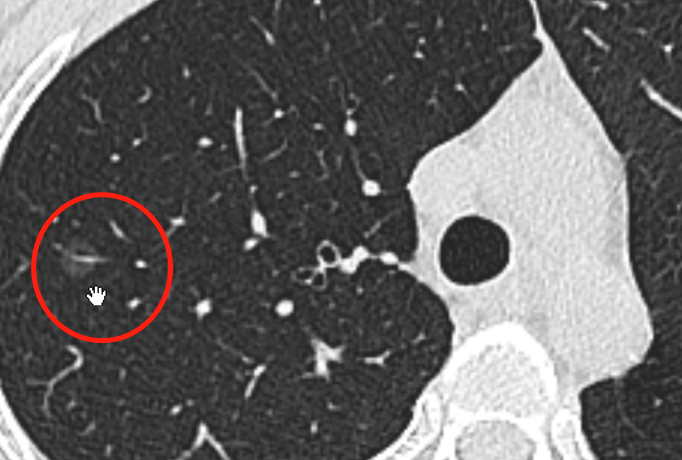

肺癌,尤其是年轻人发现肺癌,发现得早还好说,如果发现晚了,治愈率非常低。大家特别想问肿瘤医生这个问题:年轻人有什么办法能预防肺癌呢? 首都医科大学附属北京胸科医院的杨志医生,接诊过大量中青年肺癌患者。他发现,很多肺癌患者,都有高压力下通过吸烟熬夜喝酒等方式“自我摧残”的“黑历史”。 问:这位患者是什么情况? 杨志:这是一位27岁女性,右肺上叶有一个病灶,大概0.9公分,是非常小的磨玻璃结节,特别典型。我们可以看到一个血管穿进了磨玻璃,这是一个非常危险的信号。 问:血管穿进去就不是好事了? 杨志:对,就需要积极一点治疗。一般情况下像这种微结节,患者不会出现任何症状,比如咳嗽、咳痰、咯血,或者胸闷憋气、胸疼等等,都不会出现。 问:可以说是“毫无感觉”? 杨志:是的。因为特别早期的病灶,对周围的组织没有特别明显的侵害,所以出现不了症状。但是,即使没出现症状,这个患者血管的供支也已经出现了,癌的倾向就比较大,转移的风险也开始有了。 问:血管钻进去以后它转移的风险就很大了? 杨志:相对高了,比没有进去血管要高一些。 问:后来你们怎么建议她治疗? 杨志:尽管她是27岁的女性,但我们考虑是癌的情况,跟家属进行了沟通,最后进行了手术治疗。术后病理证实是微浸润性腺癌,淋巴结也没有转移,是早期肺癌。所以她的生存期应该会非常好,五年生存率应该接近100%。 问:这也是一个非常幸运的孩子,她又是怎么发现的? 杨志:她也是体检发现的,但不是一个普通体检。这个病人是因为疫情原因,住院患者若需要陪护家属,这个配合家属就需要做CT筛检。这个病人有一个亲戚受伤了,外伤,她来陪护,所以她就做了CT检查,很幸运,提早发现了问题。 问:像她这个年纪,如果按照一般建议的40岁以后再做CT,就是13年过去了,13年过去肿瘤可能会发生什么? 杨志:13年过去可能等不到体检发现了,可能后期症状都会出现。 问:等症状出来就可能晚期了? 杨志:等症状出来,就像我们之前说的,五年生存率断崖性下跌,到50%之下。 问:她的父母有肺癌病史吗,还是家族里有人有癌症病史? 杨志:患者父母或者其他直系亲属没有癌症病史,但是这个病人精神压力比较大,据她父母说,她平时情绪不是特别好,精神压力极大,这种情况有可能诱发癌症的产生。 问:现在年轻人肿瘤的发现的越来越多,如果总结一些规律的话,年轻人肿瘤有没有一些共性的,或者说可以让其他年轻人也注意的问题? 问:也就是说,工作压力和学习压力不可避免,年轻人该拼搏也得拼搏,但这时候人的抵抗力会下降,所以这种时候我们尽量少做一些雪上加霜的事情,像抽烟、熬夜、暴饮暴食……可能会让这些东西趁虚而入。 杨志:对。我们越是在高压的时候越要保护身体,越是在高压的时候越应该合理安排时间,更好的保护自己各器官的健康。 问:像这女孩也是在精神上有巨大的压力吗? 杨志:据她父母说,这个病人之前有过自杀的情况,有过抑郁症的病史,她精神压力比较大。过高的精神压力,可能对身体的免疫力破坏比较大,免疫力低了之后,癌细胞有可能趁虚而入。 问:要是这种情况的话,是不是可以这样想:比如说一个年轻人,他可能还没到40岁建议做CT的年纪,但是他经历了一段工作压力很大的阶段,而且那段时间也不小心又是熬夜又是吸烟。像这种情况下,过后,他是不是赶紧去拍个CT排查一下? 杨志:如果我们大家都有这种意识,我们就会有一个更好的结果。这就有点像汽车的保养,比如说我明天放假了,我要去开车去西藏,那我首先需要查一查汽车,回来之后再查一遍汽车,轮胎可不可以,发动机行不行。人也是一样。人比机器更复杂,所以我们也更应该更好地保护我们自己的身体。 最后杨志医生总结,虽然无法证明肺癌和压力情绪的直接关系,但是精神压力和不规律生活会降低机体免疫力,而低免疫力是肺癌的诱因之一。他治疗的年轻患者当中,多见高压加上“自我摧残”的“黑历史”。杨志医生给的建议就是,年轻人在工作压力大,情绪高度紧张的时期,尽量避免熬夜吸烟喝酒等等自我摧残的坏习惯,让免疫系统喘口气,增强人体对于疾病的抵抗力。